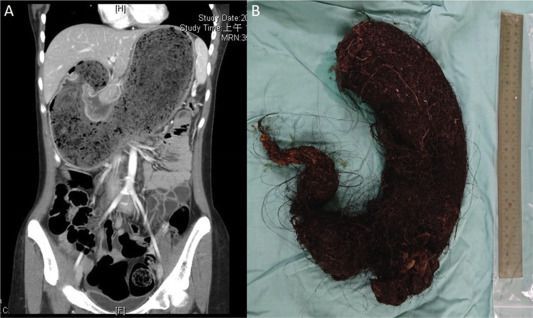

A 16 years old girl with a past history of tricophagia and microcytic anemia was presented with anorexia, vomiting, and weight loss for 2 months. On examining her abdomen, a large non-tender mass was palpable in the left upper quadrant. Abdominal CT showed large amounts of mottled material in the stomach, presumed to be a bezoar. On anterior gastrotomy, a trichobezoar was seen completely filling the stomach and extending into the duodenum. Upon histopathological examination, it was found to be a hairball containing food residue. Surgical excision of the bezoar was done and the patient was referred to the psychiatry department. A bezoar is a collection of non-digestible materials in the stomach or intestine. A trichobezoar refers to hairballs in the stomach, almost exclusively found in young female psychiatric patients. Most of the cases are asymptomatic until the mass reaches a size large enough to cause symptoms. If left untreated, it can cause perforation, gastric ulcers, and even death. Diagnosis is made by abdominal ultrasound and CT scan. Conventional laparotomy is the treatment of choice. Reference: https://www.pediatr-neonatol.com/article/S1875-9572%2819%2930520-0/fulltext